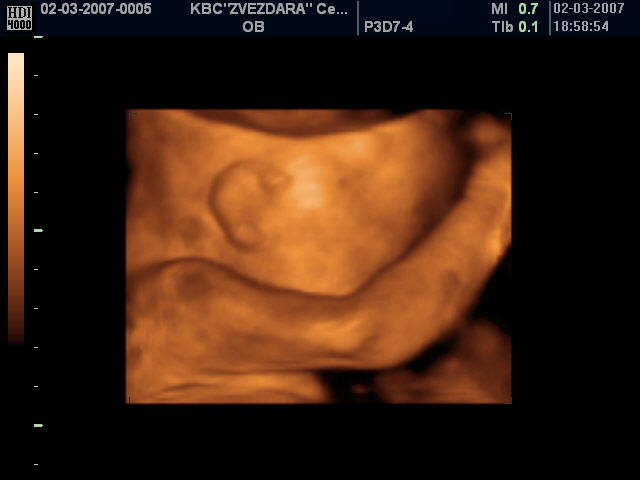

Снимак детета у стомаку мајке 3Д ултра-звуком:

78 % жена које виде ултра-звук бебе одбијају абортус! - погледајте

Већина лекара који изводе чедоморства ради новца не дозвољавају мајкама да виде своје дете на ултразвуку нити да чују његове откуцаје срца да не би промениле одлуку.